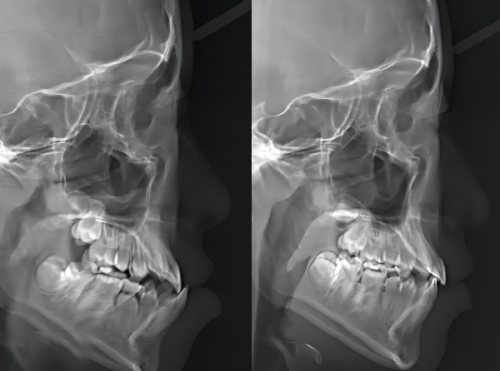

1. **核心设备精良**:宜宾为笑口腔医院配备了德国卡瓦大视野CBCT(骨量测量误差<0.1mm)、3D数字化导板导航系统(微创种植创口<3mm)、iTero口扫仪(隐形矫正方案精度达20μm)等一系列精良的口腔医疗设备。这些设备的引进,使得医院能够更加精细地诊断和治疗各种口腔疾病,提高了治疗成效和患者的满意度。

2. **矫正医生**:医院的矫正医生团队同样非凡,李明锦医生是正畸学硕士,索利利医生是隐适美认证医师,他们的骨性错颌矫正成功几率达92%。他们能够根据患者的不同情况,制定个性化的矫正方案,帮助患者实现整齐美观的牙齿。